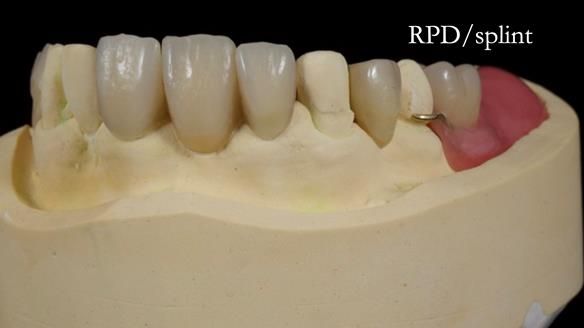

This edition features the case of Edgar, who sought help for a poorly fitting, acrylic-based partial denture that rocked, affected his speech, and caused discomfort. After considering various treatment options, including dental implants, Edgar opted for a metal-based removable partial denture, designed by myself with input from my technician, Rowan Garstang.

Treatment Process: I provided the clinical work while Rowan Garstang delivered the technical aspects. The treatment required fifteen visits to fit and review Edgar.